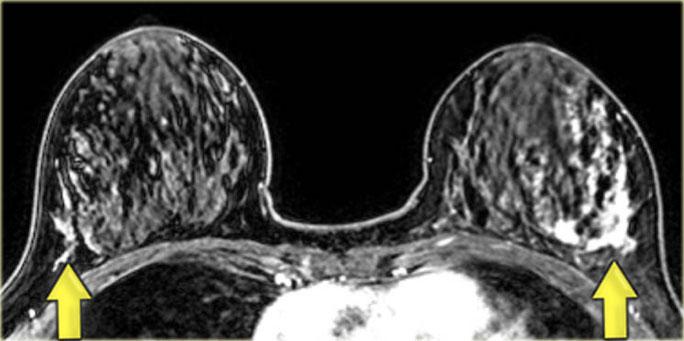

Bên trái là bệnh nhân có các vùng ngấm thuốc không tạo khối ở cả hai vú (DCIS).

Có một khối ngấm thuốc nhỏ ở phía trong vú trái, được xác định là ung thư xâm lấn nhỏ.

Một trường hợp DCIS khác, khu trú ở phía ngoài cả hai vú.